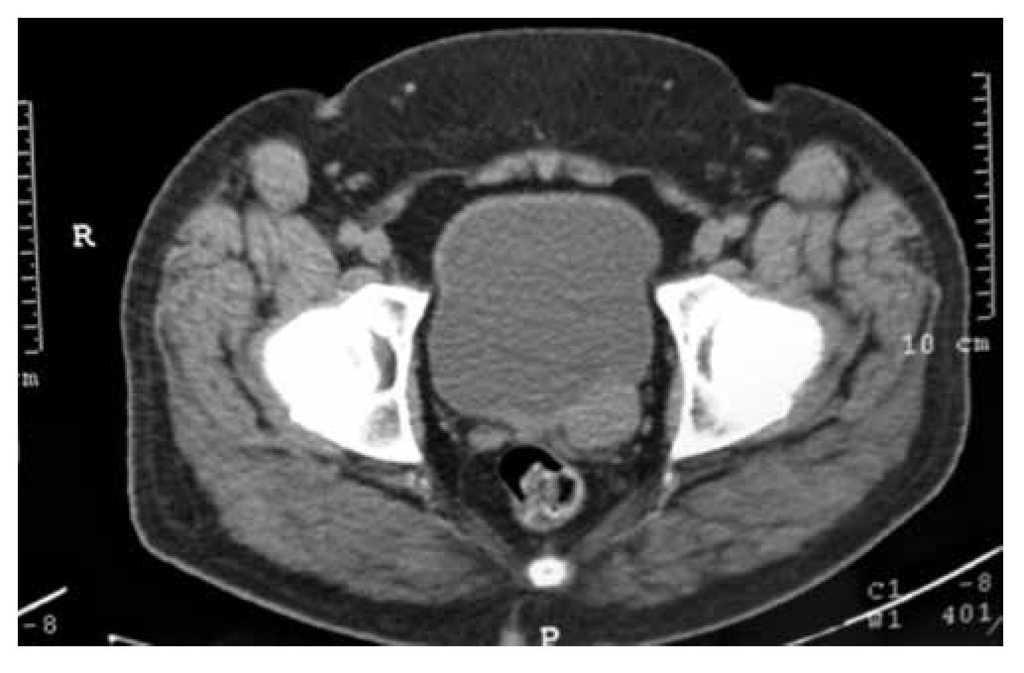

Figura 3 Tomografía computada contrastada. Se identifica nuevamente la lesión de la vesícula seminal izquierda.